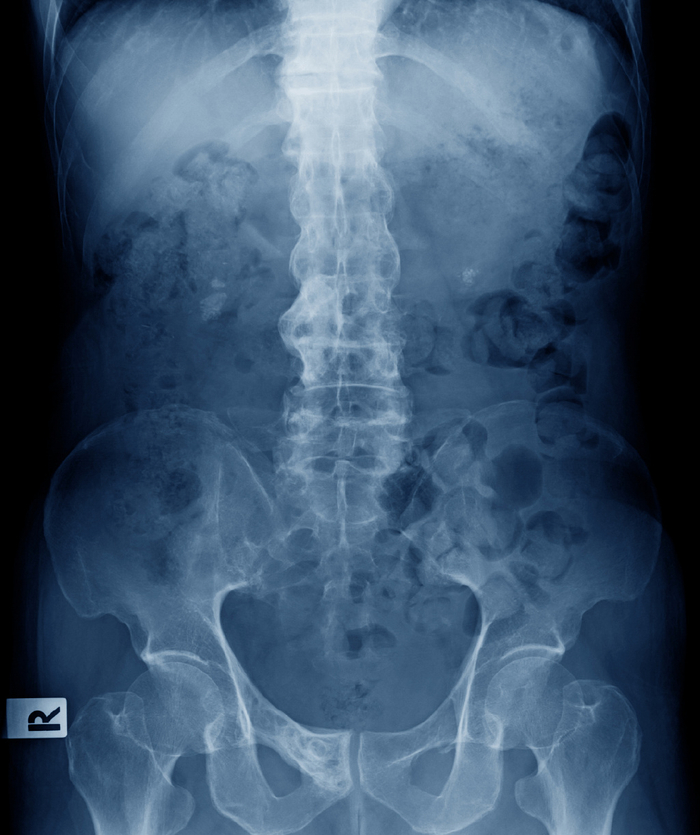

强直性脊柱炎的早期症状主要包括以下方面1 骶髂关节疼痛早期症状多集中于腰背部,尤其是骶髂关节区域位于骨盆与脊柱连接处患者常感到隐痛或钝痛,可能单侧或双侧出现,休息时加重,活动后缓解疼痛可能放射至臀部或大腿后侧,但较少涉及膝关节以下2 晨僵现象晨起时腰背部僵硬是典型表现。

强直性脊柱炎早期症状主要包括以下方面一腰背部症状早期常表现为隐匿性发作的腰背部疼痛,疼痛部位以骶髂关节下腰部为主,持续时间超过3个月疼痛特点为休息时加重,活动后稍缓解,并可能随病情进展逐渐向上蔓延至胸椎颈椎研究显示,约90%的患者早期出现骶髂关节受累相关的不适,年轻男性16。

强直性脊柱炎早期症状主要包括以下方面1 晨起腰背僵硬或疼痛强直性脊柱炎早期最典型的症状是晨起时腰背部僵硬感或隐痛,活动后症状可逐渐缓解这种僵硬感通常持续30分钟以上,严重者可能影响翻身或起床动作其本质是骶髂关节及脊柱小关节的炎症反应,导致关节周围韧带和肌腱附着点病变2 下肢大关节。